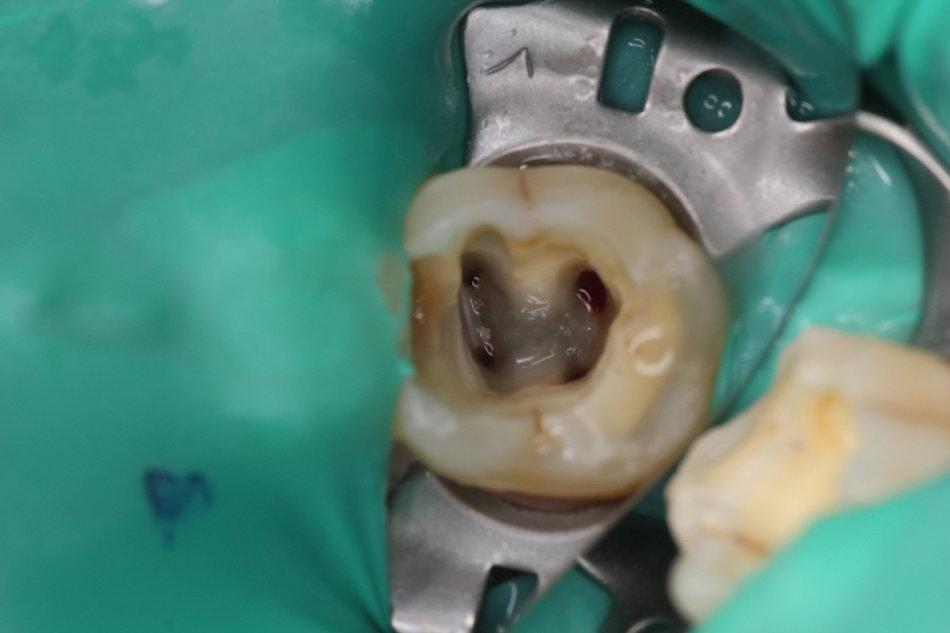

现在很多人都会蛀牙,然后很多人发现蛀牙的时候,往往都是比较严重了,需要进行根管治疗——也就是要截取牙神经。

不能。一般需要进行根管治疗的牙齿,说明都已经进入了感染期,牙齿是会有较大的疼痛感的。如果不进行根管治疗,炎症只会越来越厉害,最终有可能导致牙齿真的保不住——松动,掉落。